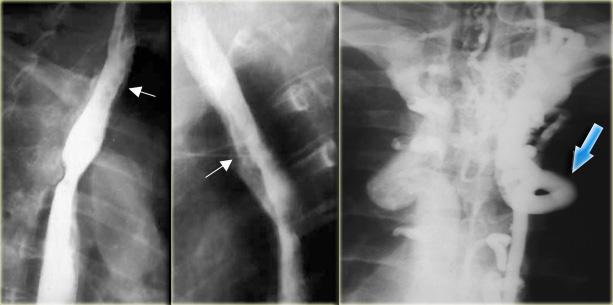

TRÁI: Hẹp đoạn xa dài và không đều do ung thư. PHẢI: Hẹp đoạn xa không có dạng thuôn nhọn và ở vị trí gần hơn so với co thắt tâm vị. Sự không đều (mũi tên) tại vị trí hẹp tinh tế nhưng dai dẳng.

Ngoài cùng bên trái là hình ảnh bệnh nhân ung thư có hẹp thực quản.

Hẹp không đều, không đối xứng gợi ý mạnh đến ung thư.

Hẹp thuôn nhọn đều đặn, đối xứng là đặc trưng của nguyên nhân lành tính, tuy nhiên các hẹp ác tính cũng có thể có đặc điểm tương tự và bắt chước tổn thương lành tính.

Kế bên là hình ảnh bệnh nhân ung thư có hẹp thực quản giống co thắt tâm vị.

Bệnh lý ác tính đoạn thực quản xa có thể rất giống co thắt tâm vị.

Nếu nhu động thực quản bình thường, có thể loại trừ co thắt tâm vị.

Tuy nhiên, nếu bất thường, các đặc điểm hình ảnh tinh tế như: hẹp không đối xứng, không đều, đột ngột hoặc ở vị trí cao, bất thường niêm mạc, hoặc bất thường cố định sẽ gợi ý chẩn đoán.

Bên trái là một trường hợp giả co thắt tâm vị khác.

Hẹp đoạn xa mô phỏng co thắt tâm vị, nhưng vị trí hẹp lệch tâm, các bờ vai không đối xứng (mũi tên), và niêm mạc không đều tại đỉnh vùng hẹp.

CT cho thấy thành đáy vị dày lên (mũi tên) do ung thư biểu mô tuyến.